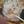

12W去医院,B超医生说宝宝偏小两天,位置也不对,让星期五再去,今天12+4,宝宝很配合,但不知道为什么还是做了很长时间,差不多一个小时了,老公在外面都等的担心了,生怕有什么不好的,看到宝宝滑动 翻跟头 嘴巴吧唧 好可爱 听到了小火车的声音 很开心❤️但是小家伙总是用手挡住鼻子,导致看鼻骨看了好半天,医生还说好像连接不上,是不是有缺,吓死我了,好在后来晃了几下小家伙把手手拿开了,看到鼻骨连接上了,这才放心下来,顺利进入孕中期啦 开心😬😬小家伙 接下来我们一起加油好好成长哦😘😘传大家NT顺利通过 愿我们产检一路绿灯 宝宝健康成长平安足月出生✌✌